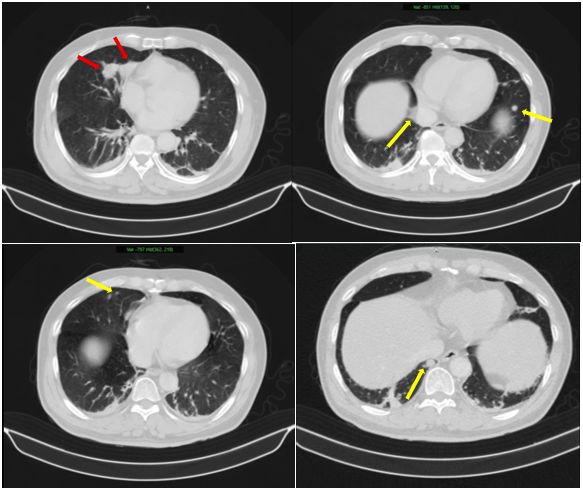

Sau đó, bệnh nhân được bổ sung các xét nghiệm đánh giá toàn thân. Kết quả phim chụp cắt lớp vi tính ngực và bụng cho thấy, không chỉ có khối u ở tuyến tiền liệt mà bệnh nhân còn có nhiều khối u khác ở phổi (Hình 2), tuyến thượng thận (Hình 3) và xương (Hình 4).

Hình 2: Hình ảnh 02 khối u bờ đa cung ở nhu mô thùy giữa phổi phải, dính vào màng phổi trung thất (mũi tên đỏ) kèm nhiều nốt đặc nhỏ rải rác nhu mô phổi hai bên (mũi tên vàng) gợi ý tổn thương thứ phát.

Hình 3: Hình ảnh dày tuyến thượng thận phải tạo nốt có kích thước 19 x 17 mm (mũi tên đỏ).